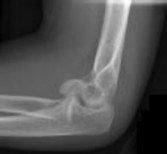

Figures 1 and 2 are the radiographs of a 35-year-old man who has elbow pain after falling from a ladder onto an outstretched hand. Examination reveals elbow pain, swelling, limited motion, and normal neurologic function.